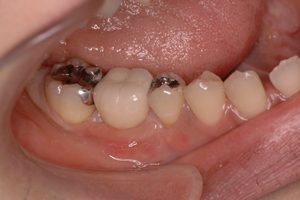

6.<仮歯の装着>

二次手術後の歯茎の治りを待って、仮歯を作製し、インプラントに負荷をかけていきます。それと同時に実際に使用してもらいながら、噛み合わせ、清掃性を調整します。

状態によって異なりますが、1~3ヶ月ほど経過を診ていきます。

7.<最終的な歯の装着>

仮歯の調整で得た情報を最終的な歯の作製に反映させていきます。最後に歯の色を確認して装着します。

最終的な歯の作製にはおおよそ1ヶ月ほどかかります。